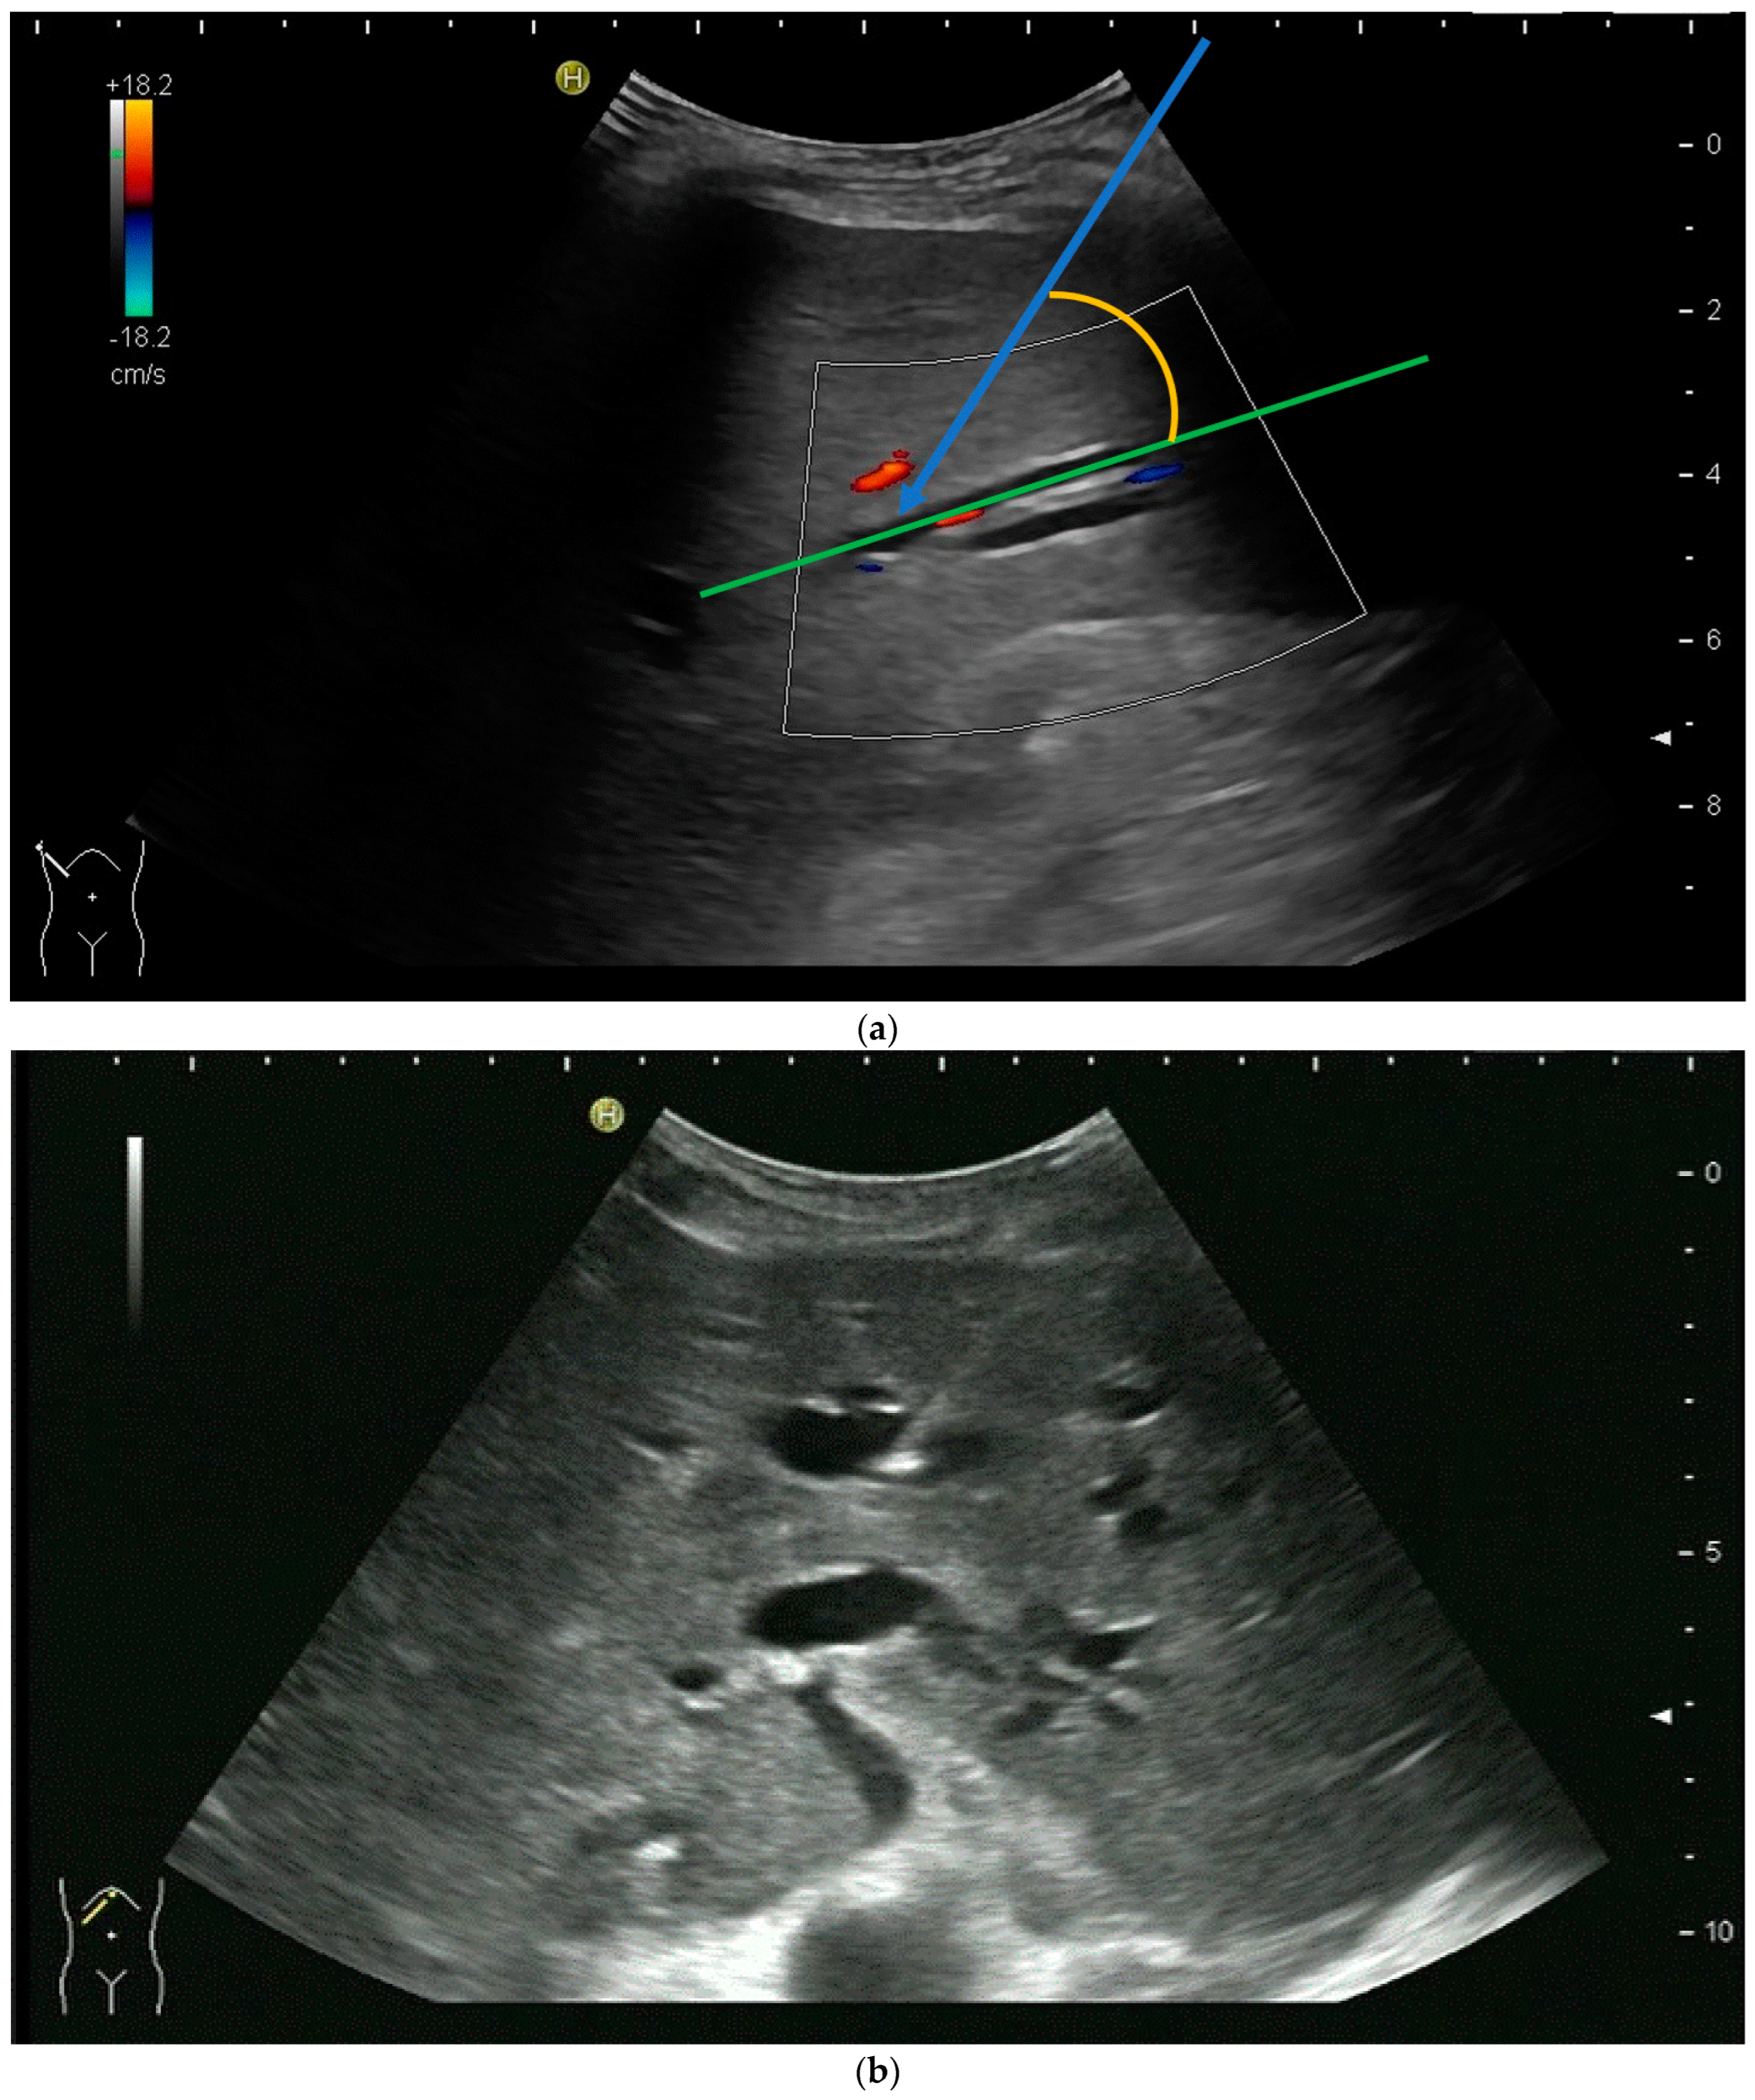

However, the “free hand” technique allows for every puncture angle and is, therefore, preferred by us. The use of colour Doppler will enable the doctor to avoid blood vessels and identify smaller bile ducts (Figure 3a,b).

Figure 3.

(a) Hypoechoic tubular structures in Segment V are visualised in an intercostal view; (b) Colour Doppler helps to differentiate between bile ducts and blood vessels.

In cases of extrahepatic obstruction, mostly the right liver lobe will be addressed. It is common practice to head for the peripheral branches in Segment V (cf. Figure 3a,b), as from there to the common bile duct, the biliary branches form a harmonic arch, and the forward movement of the guide wire seems unpretentious [3]. However, US guidance allows the puncture of any biliary duct of the right or left liver lobe that can be depicted well (Figure 4a–c).